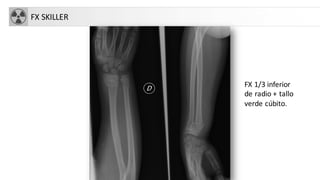

FX SKILLER

FX 1/3 inferior

de radio + tallo

verde cúbito.

FX SKILLER FX 1/3inferior de radio + tallo verde cúbito.